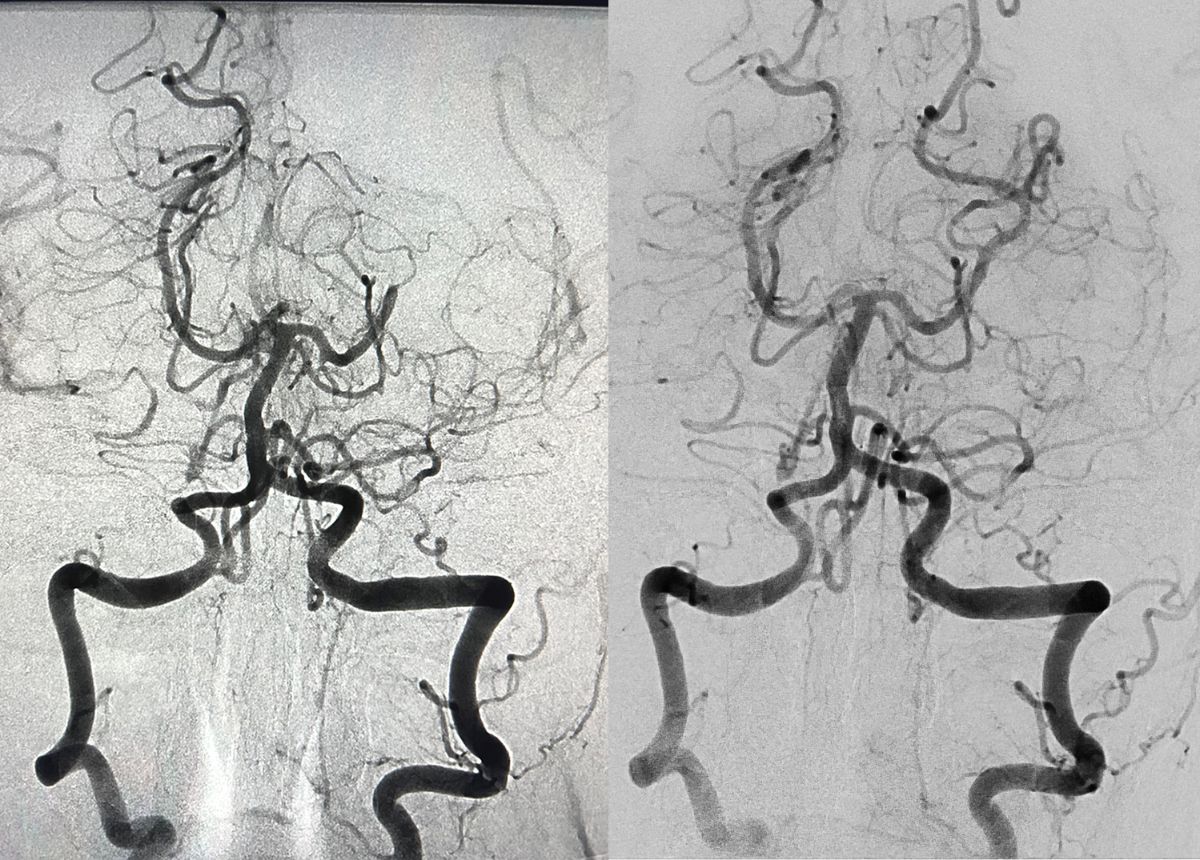

Was macht man in der interventionellen Radiologie?

Die interventionellen Radiologie ist spezialisiert auf die Diagnostik und Therapie von Gefässkrankheiten, Entzündungen, Tumoren und Schmerzen.

Deren Ursachen werden mithilfe kleinster Instrumente gezielt und möglichst schonend behandelt. Die Behandlung wird daher als minimalinvasive Therapie bezeichnet.

Auf diesen Angiografie-Bildern sieht man die hintere Gehirnarterie: vor (links) und nach der Entfernung eines Gerinnsels (rechts).